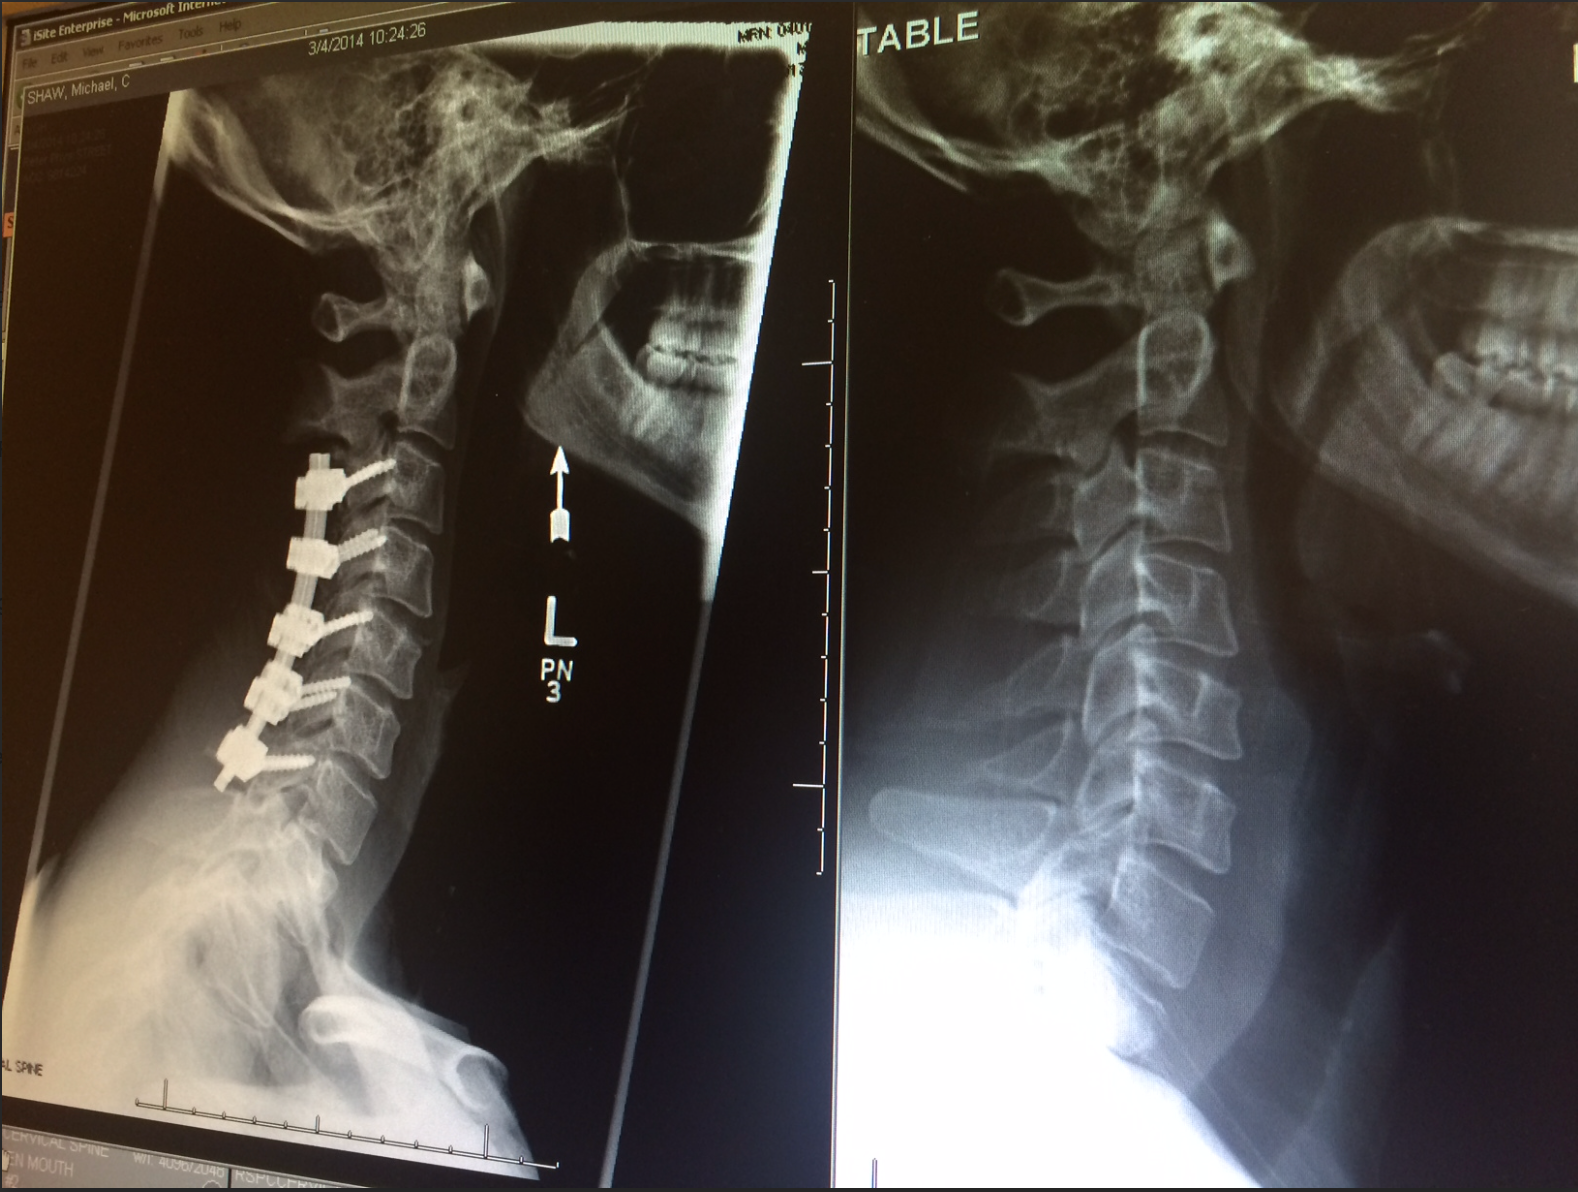

On December 16, 2013, my life took an unexpected turn. I dislocated my neck in a tragic skiing accident, rendering me paralyzed from the neck down and hanging on for dear life. As the head coach of the Canadian Olympic Development HalfPipe Ski Team, my world came crashing down.

The spinal specialist gave me their evidence and judgment—my imaging scans “looked bad.” My surgeon agreed, “Mike, it really doesn’t look good.”

I walked out of the hospital after just three and a half months. After one year, I stepped back into a pair of skis. As time went on, I climbed mountains, took on the steepest running race in the world (the Red Bull 400), ran the Wings for Life World Run year after year, started multiple businesses, shared my story from the stage in front of thousands all over the world, conquered significant backcountry skiing objectives, and even ran a marathon—milestones that are difficult for most people to accomplish, let alone most quadriplegics.

My near-death experience gifted me a perspective of profound gratitude. I have been given a second chance at life with an able body. I still have symptoms of my spinal cord injury, including limited feeling in my hands and legs, dexterity issues, and compromised balance and coordination. My body isn’t perfect, but it’s mine, and I’m lucky to have the abilities I do, so I choose to make the absolute most of them.